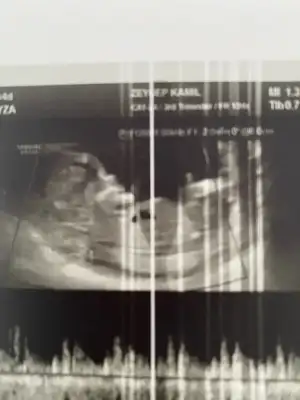

Cinsiyet tahmini yapan arkadaşlar bakabilir misiniz? Doktor %90 bir şey söyledi ama önceki doktor da başka bişey dediği için size sormak istiyorum. 12+6

Geçen haftakine siz de kız yazmıştınız sanırım, yani 3 kişi kız yazmıştı, erkek yazan yoktu, bu hafta erkek dedi.

O zaman sen biraz daha bekle 16 haftayı. Değişedebilir o. Ben bunda nub göremedim görsem garanti gibi o aslında. Kemik yapısını erkeğe benzettim ki o garanti değil. %90 diyen doktorun dediği doğrudur bence yüksek bi oran. Biz doktor kadar anlamayız tahmin yürütüyoruz